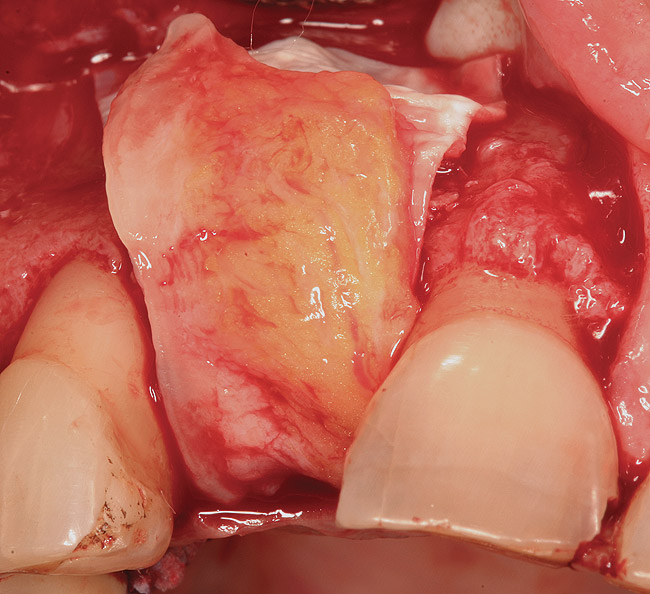

Figure 14  (Case 2) Failed implant at surgical exposure.

Figure 14

A 53-year-old woman presented with a failing implant in the No. 7 site (Figure 12 and Figure 13). Her desire was to eliminate infection and preserve esthetics. A team effort between the periodontist and restorative dentist to advocate for additional restorative dentistry as well as manage the patient’s expectation of time required was essential. In addition, the patient needed to have realistic expectations of a compromised outcome. Both the restorative dentist and the periodontist informed the patient about the difficulty of achieving this with acceptable esthetic results. Mutual emotional and technical support was required to successfully complete this case, from initial grafting of the defect to placement of anterior restorations (Figure 14 through Figure 23).